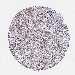

CANCER LUNG CANCER Show tissue menu

Lung cancer

Human cancer

Lung adenocarcinoma

Lung squamous cell carcinoma